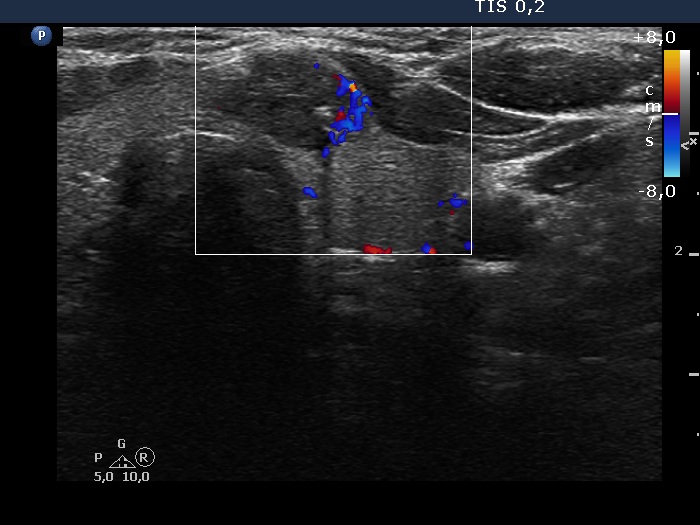

Extrathyroidal spread - case 2069 (ultrasonographic picture 4)

Left lobe, transverse scan, color Doppler mode. There are relatively large vessels in the lateral part of the nodule.